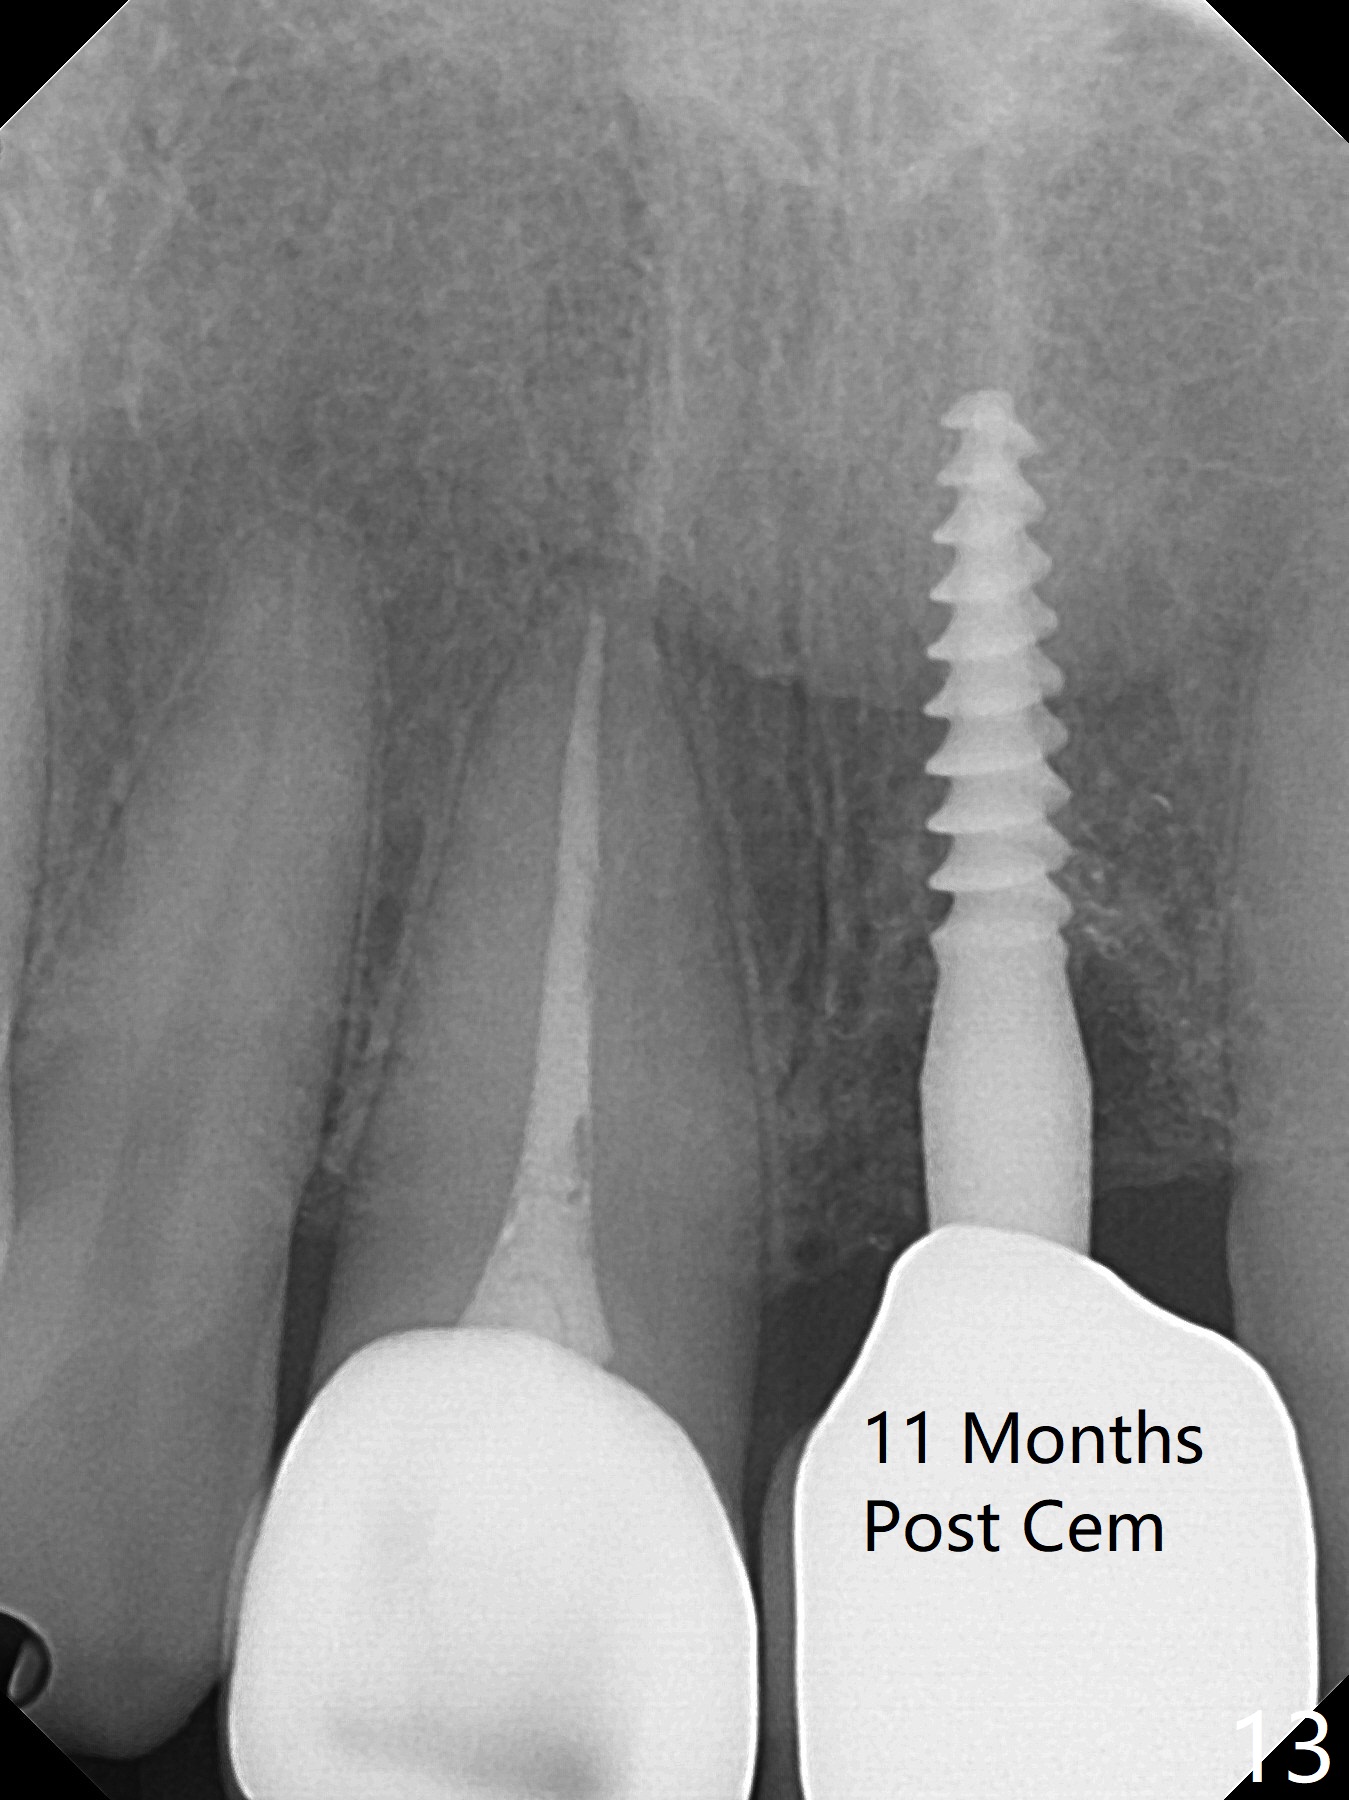

Except the depth, a 2.5x10 mm mini implant is placed with precision (in trajectory) at #9 (Fig.1-5). Confidence using surgical guide for the narrow ridge is enhanced due to placement of two digits against the buccal and palatal plates for tactile sensation. The depth issue is related to overprep with 2.2 mm drills. The torque is <15 Ncm. The immediate provisional is bonded to the neighboring teeth for retention. It appears that smaller drills should be made for guided surgery (such as 1.5 and 2.0 mm). The immediate provisional looks acceptable buccal and occlusal 3 weeks postop (Fig.6,7), although the palatal gingiva is erythematous (Fig.8, which is common after use of drill for access (tissue laceration), OHI offered). Three months postop (Fig.9), the palatal gingiva looks healthy (data not shown), while there is no bone loss around the implant (Fig.10). It remains the same 5 months postop (immediately post cementation, Fig.11) and 3,11 months post cementation (Fig.12,13). The labial gingiva is healthy (Fig.14), while the palatal one is less erythematous and edematous (Fig.15) than earlier (Fig.8).